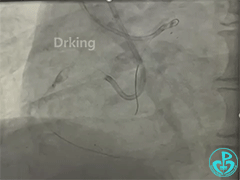

XTA、P200导丝Knuckle失败。

导丝怎么扩收藏:器械难以通过的CTO病变之技术图谱_https://www.jmylbn.com_新闻资讯_第10张

Carlino失败。

导丝怎么扩收藏:器械难以通过的CTO病变之技术图谱_https://www.jmylbn.com_新闻资讯_第11张

3.0后扩球囊Base技术。

导丝怎么扩收藏:器械难以通过的CTO病变之技术图谱_https://www.jmylbn.com_新闻资讯_第12张

XTA无法前行,P200可前行3mm左右再也不能前行。

导丝怎么扩收藏:器械难以通过的CTO病变之技术图谱_https://www.jmylbn.com_新闻资讯_第13张